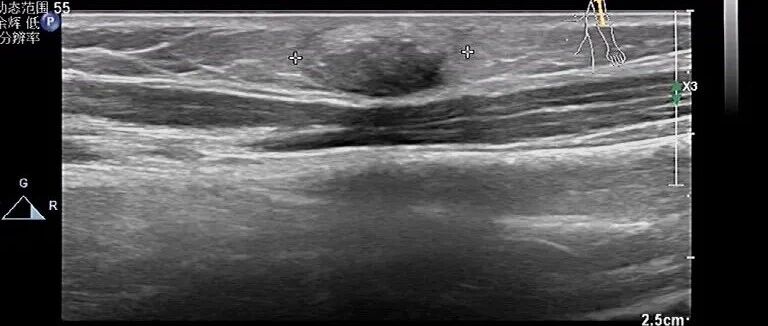

左前臂肿物,呈低回声,你考虑什么? 丁香园超声时间 · 公众号 · 医学 · 1 年前 · |